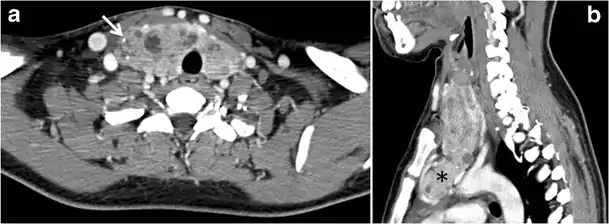

A thyroglossal duct cyst (TDC) is a duct remnant between the foramen cecum and thyroid isthmus. Most TDCs are located below the hyoid bone and in the midline. The more caudal the cyst, the more likely it will be off midline within 2 cm (Fig. 19 and and20).20). On a CT scan, a TDC appears as a well-circumscribed area of fluid attenuation with thin walls. The cyst wall can become thick with an enhancing rim indicative of current or previous infection. These cysts maybe complicated by haemorrhage, infection, or malignancy. Therefore, their US and CT scan appearance may vary based on their content. Nodular enhancement within a TDC should initiate further workup to exclude malignancy (Fig. 21). US-guided FNA of these suspicious nodular areas is considered an appropriate next diagnostic step, taking into consideration the high rate of false negative results.[1]

Fig. 20. Recurrent/residual thyroglossal duct cyst in a 39-year-old male patient. The first resection of thyroglossal duct cyst showed histopathology evidence of Hurthle cell type thyroid cancer. However, the second resection showed signs of chronic inflammation, with no malignant cells. a, b Enhanced axial and sagittal neck CT scans demonstrate a unilocular cystic lesion arising from the tongue base and extending through the partially resected hyoid bone. This cystic lesion has a peripheral enhancing wall, which becomes more thick over its inferior aspect associated with surrounding fat stranding at the surgical site (white arrow). There are no internal septations, nodules or masses, or calcifications. c Transverse view of power Doppler ultrasound at the submental area demonstrates cystic lesion and internal debris with no detected internal vascularity.[1]

Fig. 21. Papillary thyroid carcinoma arising from a thyroglossal duct cyst in a 28-year-old male. an Axial enhanced CT scan shows a large complex cystic lesion (white arrows) adherent to the anterior aspect of the hyoid bone. It has an enhancing mural solid nodules and calcifications (black arrows). There is no cervical lymphadenopathy. b Axial short tau inversion recovery (STIR) MRI image near the same level shows complex lesion of high signal intensity (long white arrows) with solid mural nodules (short white arrow). c Axial fat saturated T1 MRI image post contrast administration shows the complex cystic lesion with thick enhancing wall (long white arrows) and enhancing mural nodules (short white arrows).[1]